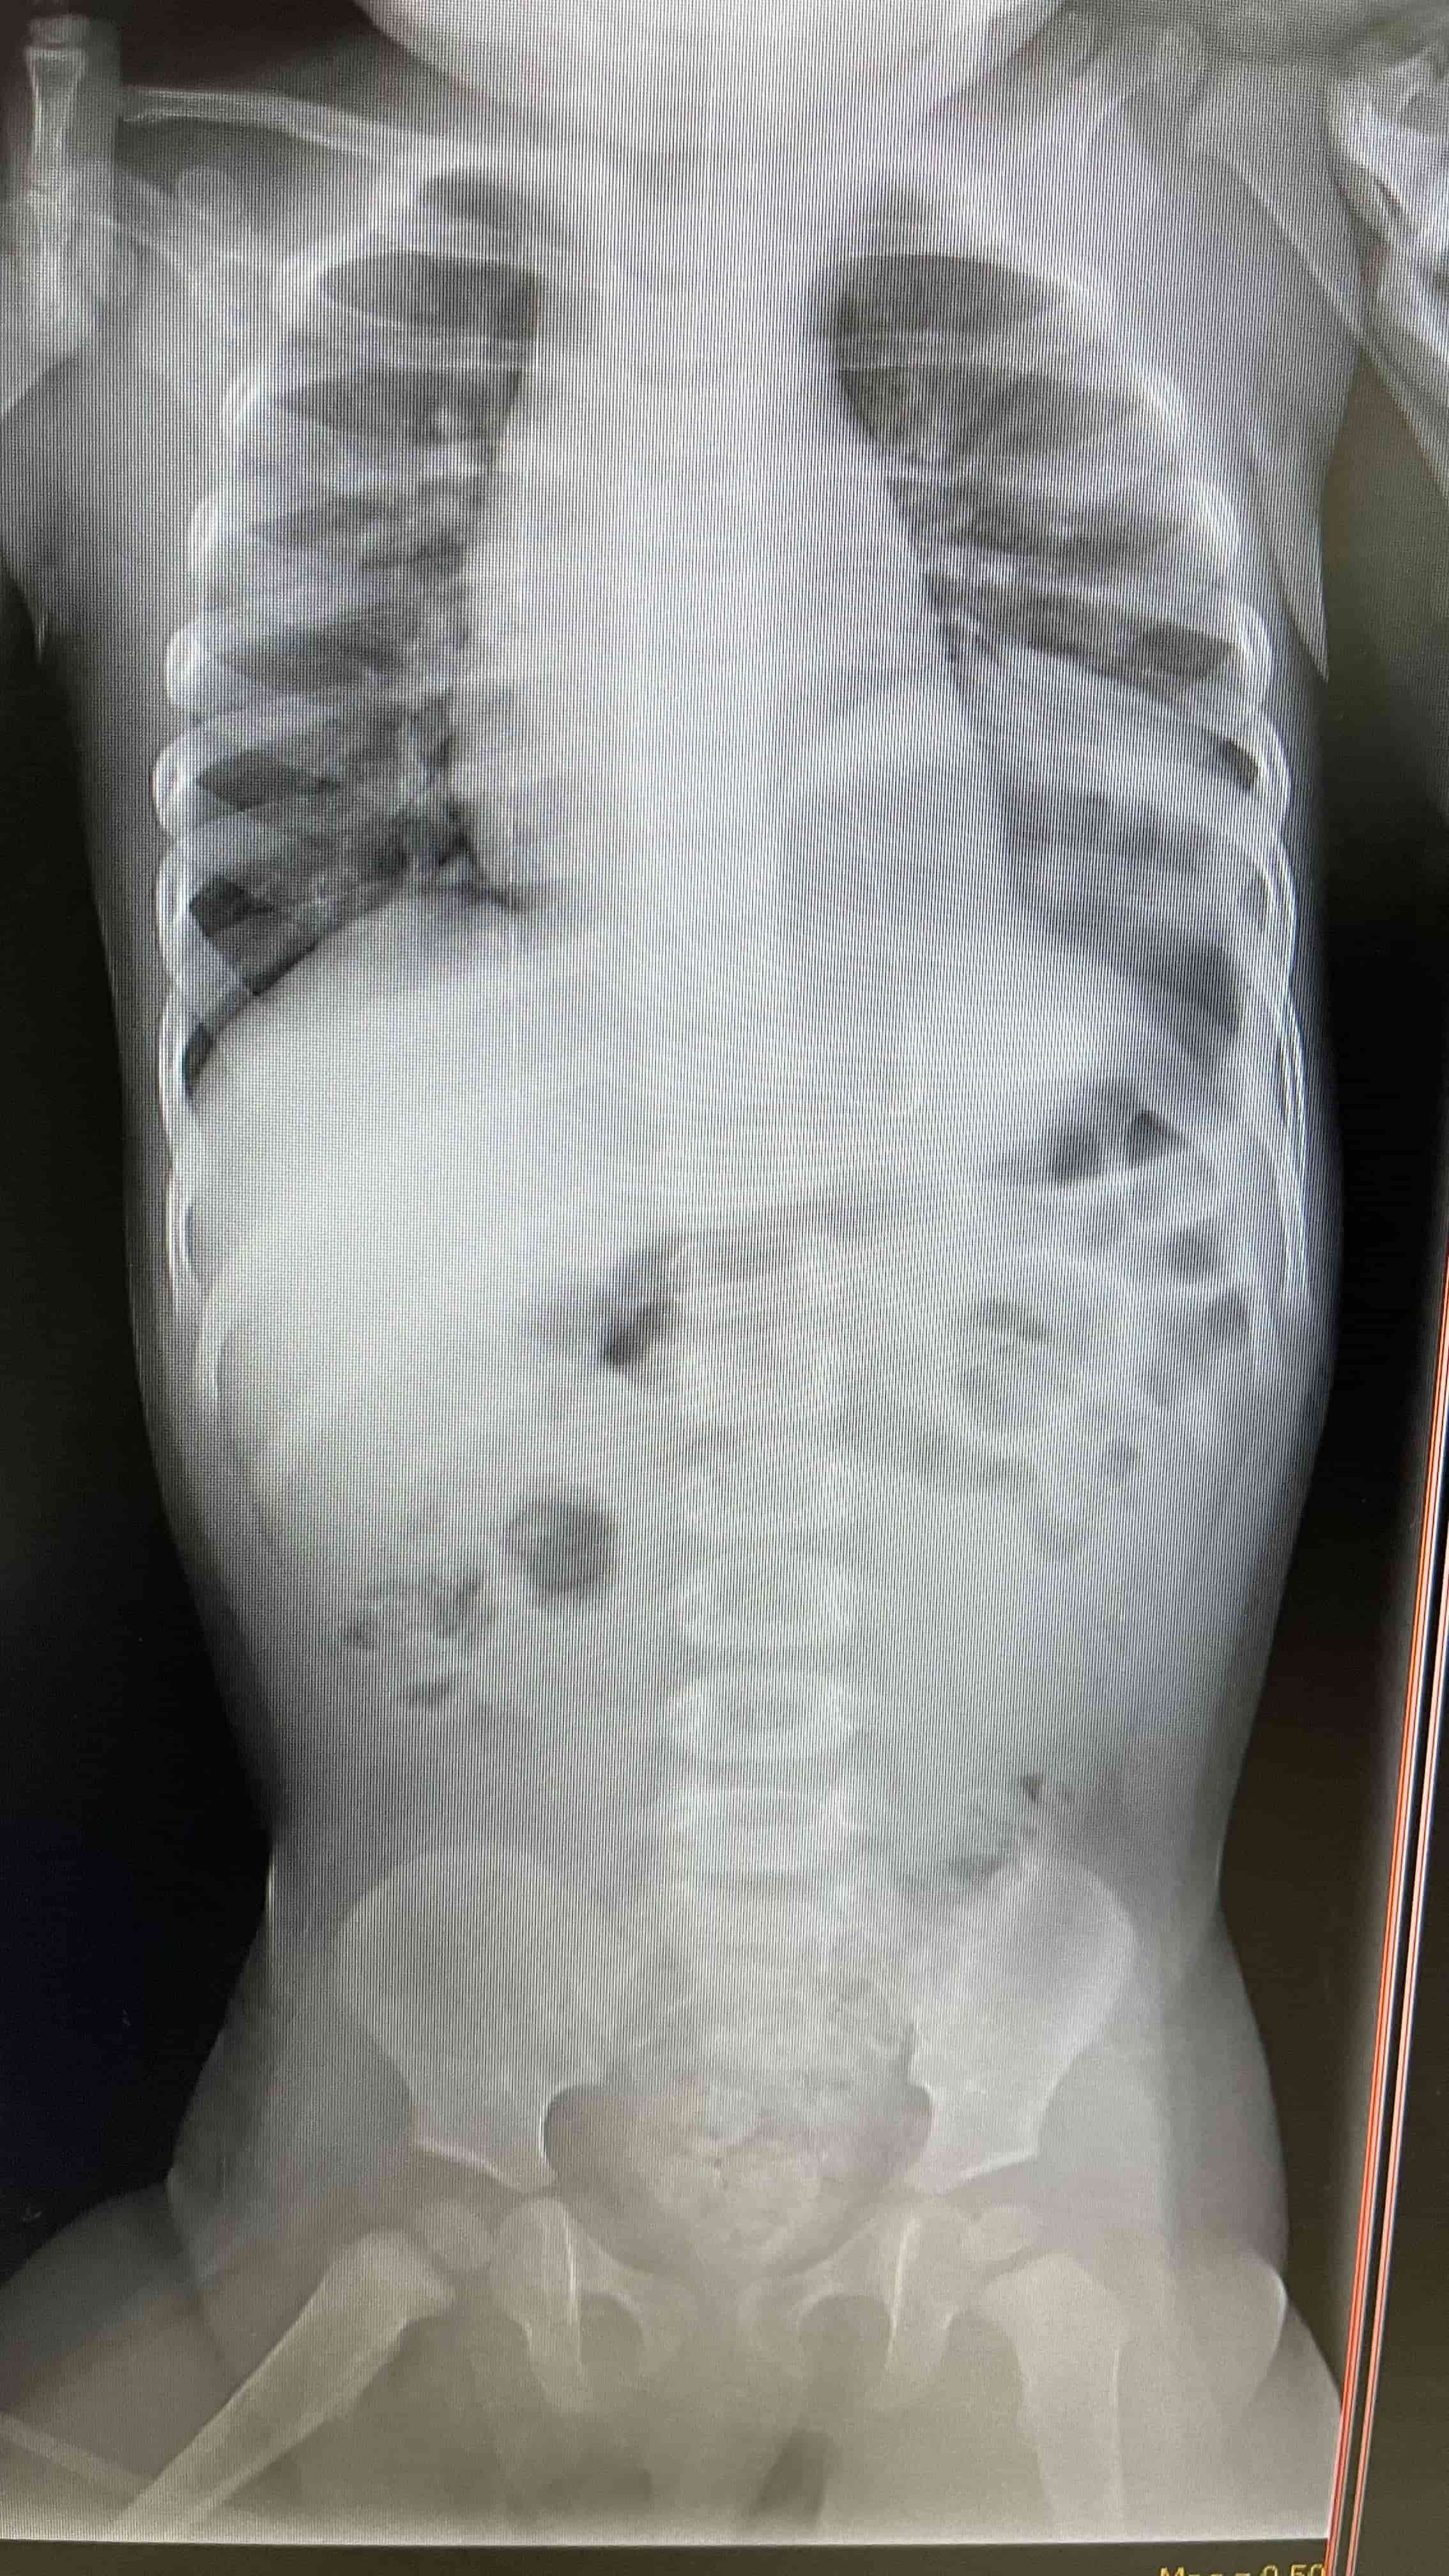

Médicos salvan la vida de infante con hernia diafragmática y estómago desplazado hacia los pulmones Radiografía de pecho y abdomen, luego de tratamiento con tubonasogástrico. Se demuestra mejoría marcada en desplazamiento deestructuras mediastinales. Médicos salvan la vida de infante con hernia diafragmática y estómago desplazado hacia los pulmones Placa lateral portable, se demuestra la hernia diafragmática Médicos salvan la vida de infante con hernia diafragmática y estómago desplazado hacia los pulmones Placa de pecho portable luego de reparación quirúrgica del diafragma.

"Tuvimos que analizar rápidamente diagnósticos diferenciales para rápido llegar al punto de lo que le estaba causando todos estos síntomas a la paciente. Se le realizaron placas de pecho y de abdomen, y ahí nos percatamos, junto a la ayuda del radiólogo, que esta paciente tenía una hernia diafragmática y que gran parte de su estómago estaba distendido y desplazado hacia el lado izquierdo del pecho, donde se supone que va el pulmón. Ahí entendimos las dificultades que atravesaba entre las náuseas, sueño y la dificultad respiratoria posicional", detallaron.

Continuaron explicando que, debido a que el estómago de esta paciente estaba distendido y lleno de aire, el diafragma presentaba un defecto al fungir como el músculo que separa los pulmones del abdomen.

"El estómago estaba tan inflamado y lleno de líquido, que empujaba las estructuras mediastinales y esto provocaba una disminución en la cantidad de sangre que llegaba al cuerpo. Tuvimos la bendición de que contamos con la ayuda del radiólogo, quien nos informó que tenía un Gastrotórax a tensión, que empujaba al mediastino hacia el lado contrario donde estaba el estómago, ocupando el espacio del lado izquierdo del pulmón, y esto demandó rápido un tubo nasogástrico -utilizado para la obstrucción intestinal-inmediatamente", establecieron.